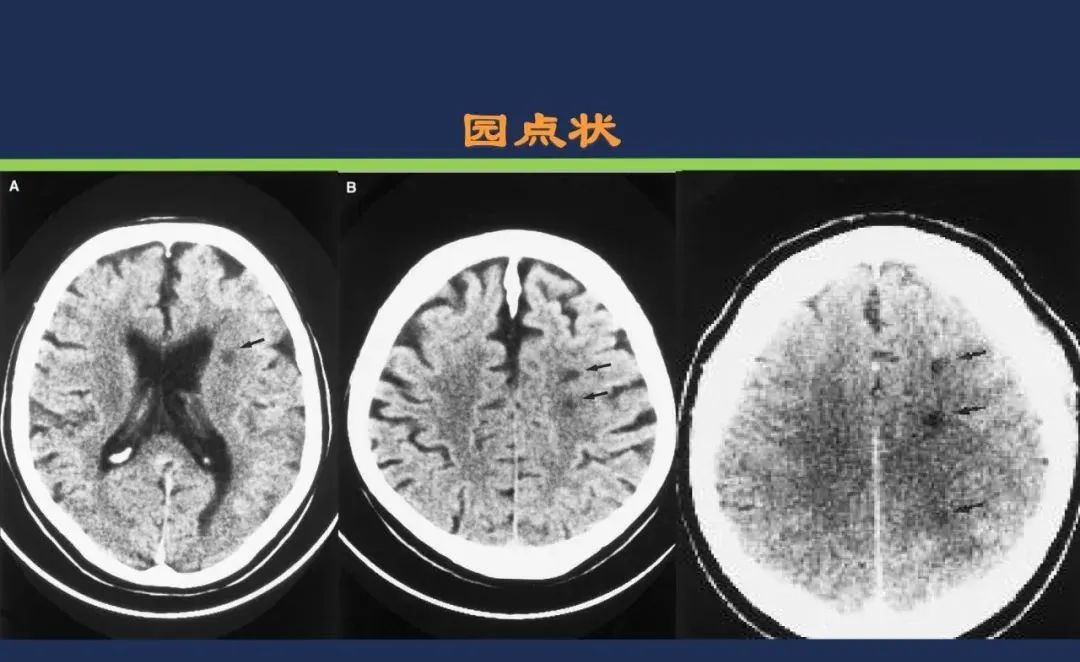

从梗死部位推测责任血管:脑血管解剖

从梗死部位推测责任血管